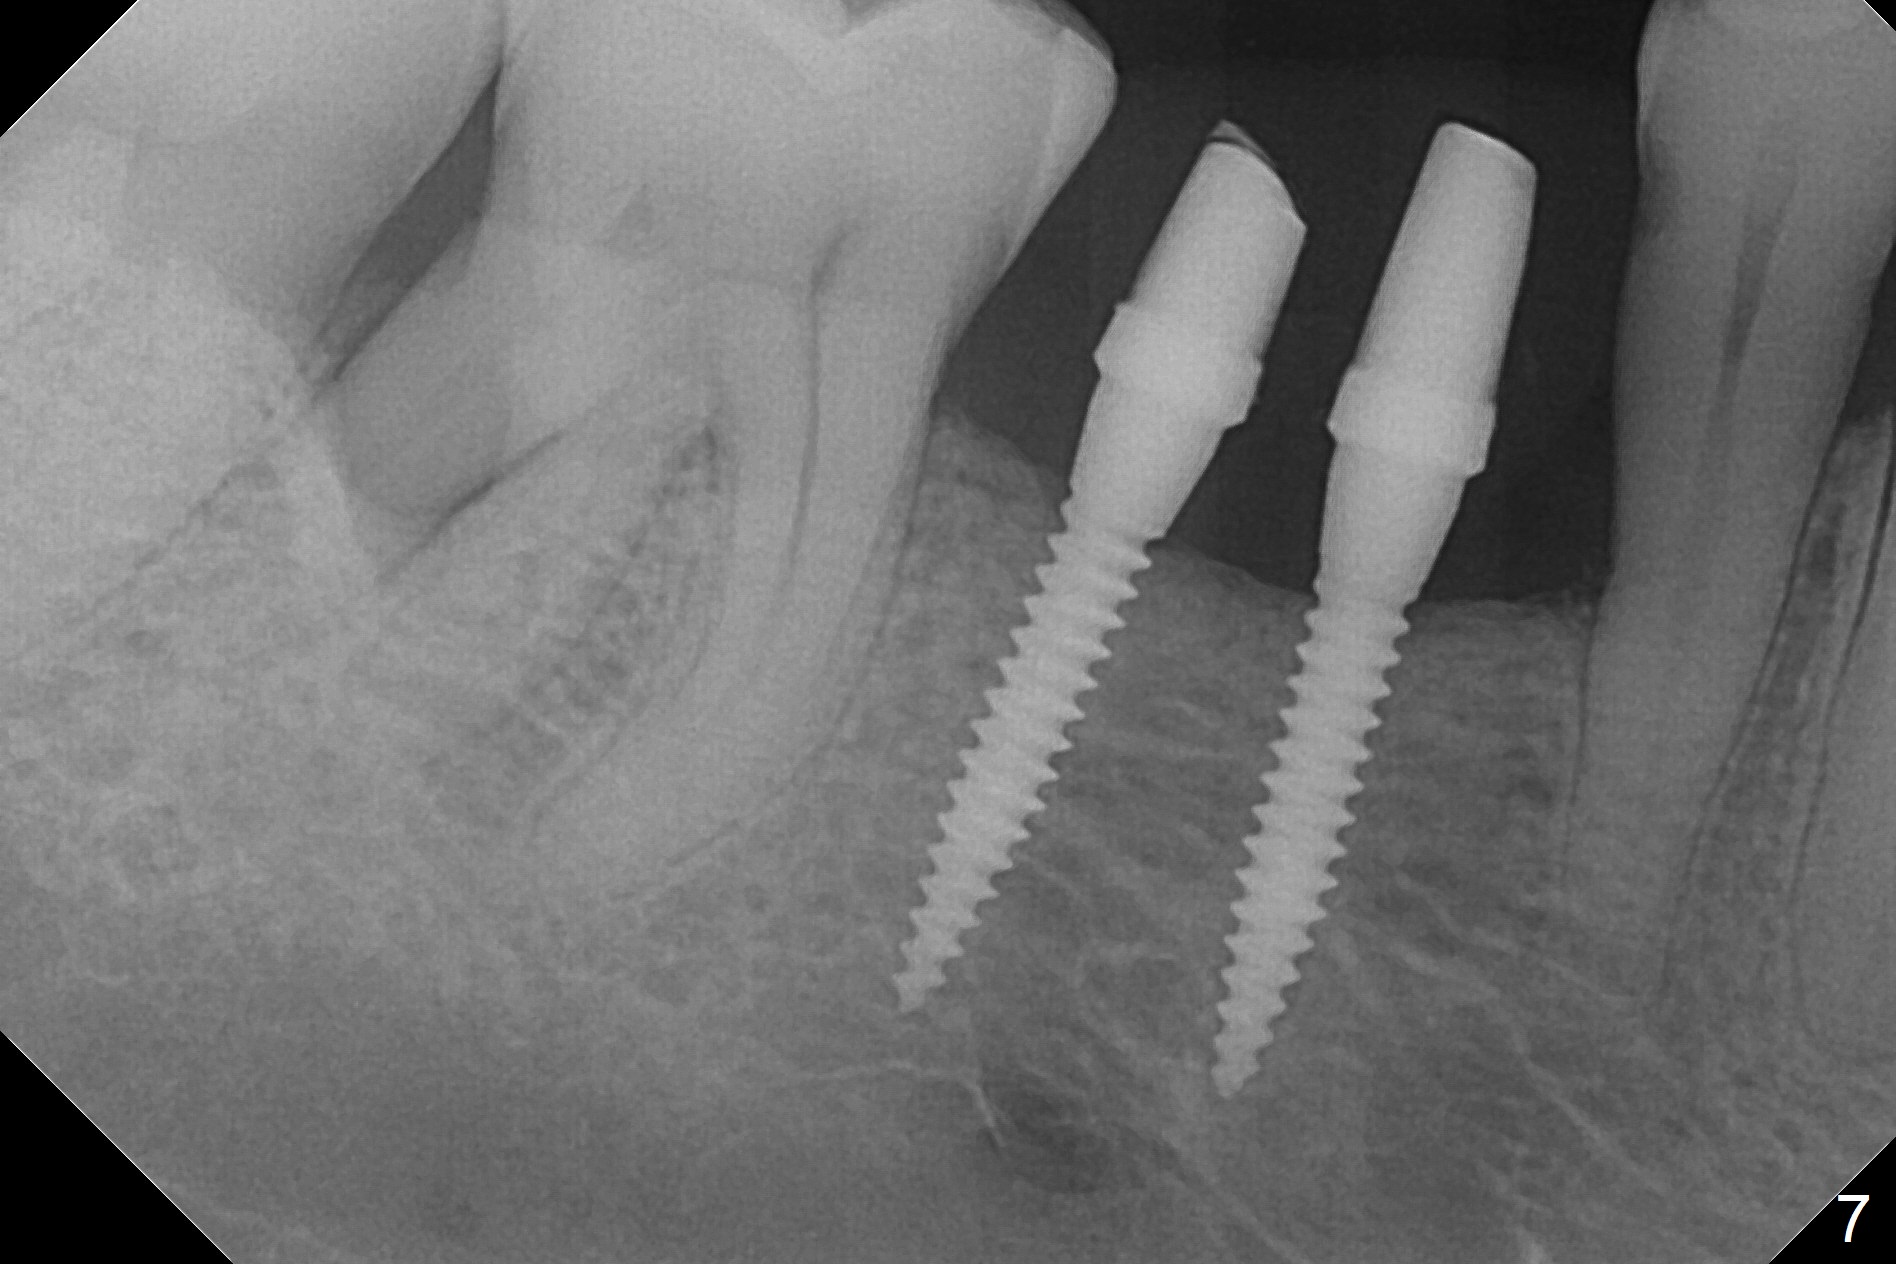

The wide mesiodistal space at #29 is most likely due to congenital missing permanent tooth (i.e., deciduous molar retention before extraction 34 years ago). The patient is now 62 years old. In fact the buccolingual width is not so narrow (Fig.1). After incision, the ridge is approximately 5 mm. Two osteotomies are established with 1.2 mm drill at 8 mm mesially and 1.5 mm one at 10 mm distally (Fig.2). The apparent approximation of the mesial osteotomy to the Mental Loop (red dashed line) is related to X-ray angulation, since there is 1-2 mm separation when two of 2x10(2) mm 1-piece implants are placed (Fig.3,4). Insertion torques of the mesial and distal implants are less than 25 and 15 Ncm, respectively. In fact bone graft is placed around the distolingual root of the tooth #30 after calculus removal (Fig.4 <). Following reduction of the abutments, periodontal dressing is applied locally. The dressing dislodged 13 days postop (Fig.5). A provisional is going to be fabricated 4 weeks postop when the wound heals (Fig.6). No bone loss is observed 4 months postop (Fig.7).